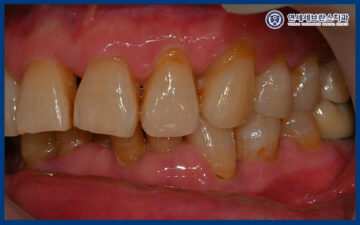

24.08.05

확인해 보니,

오른쪽 아래 통증을 느끼는 부위의

뿌리 끝 염증이 진행되어 있었는데요.

이로 인해 잇몸이 붓고

심한 압통이 동반되었으며,

일상적인 식사나 저작 시에도

큰 불편을 겪고 계셨는데요.

이러한 상태는 염증이

내부에 고여 있는 경우가 많아

자연적으로 호전되기 어렵고,

적절한 처치를 통해 염증을 배출하고

원인을 제거하는 과정이 필요합니다.

또한 다른 부위들도 치아가 부러지거나

충치가 생겨 치료가 필요한 부위가 많았습니다.